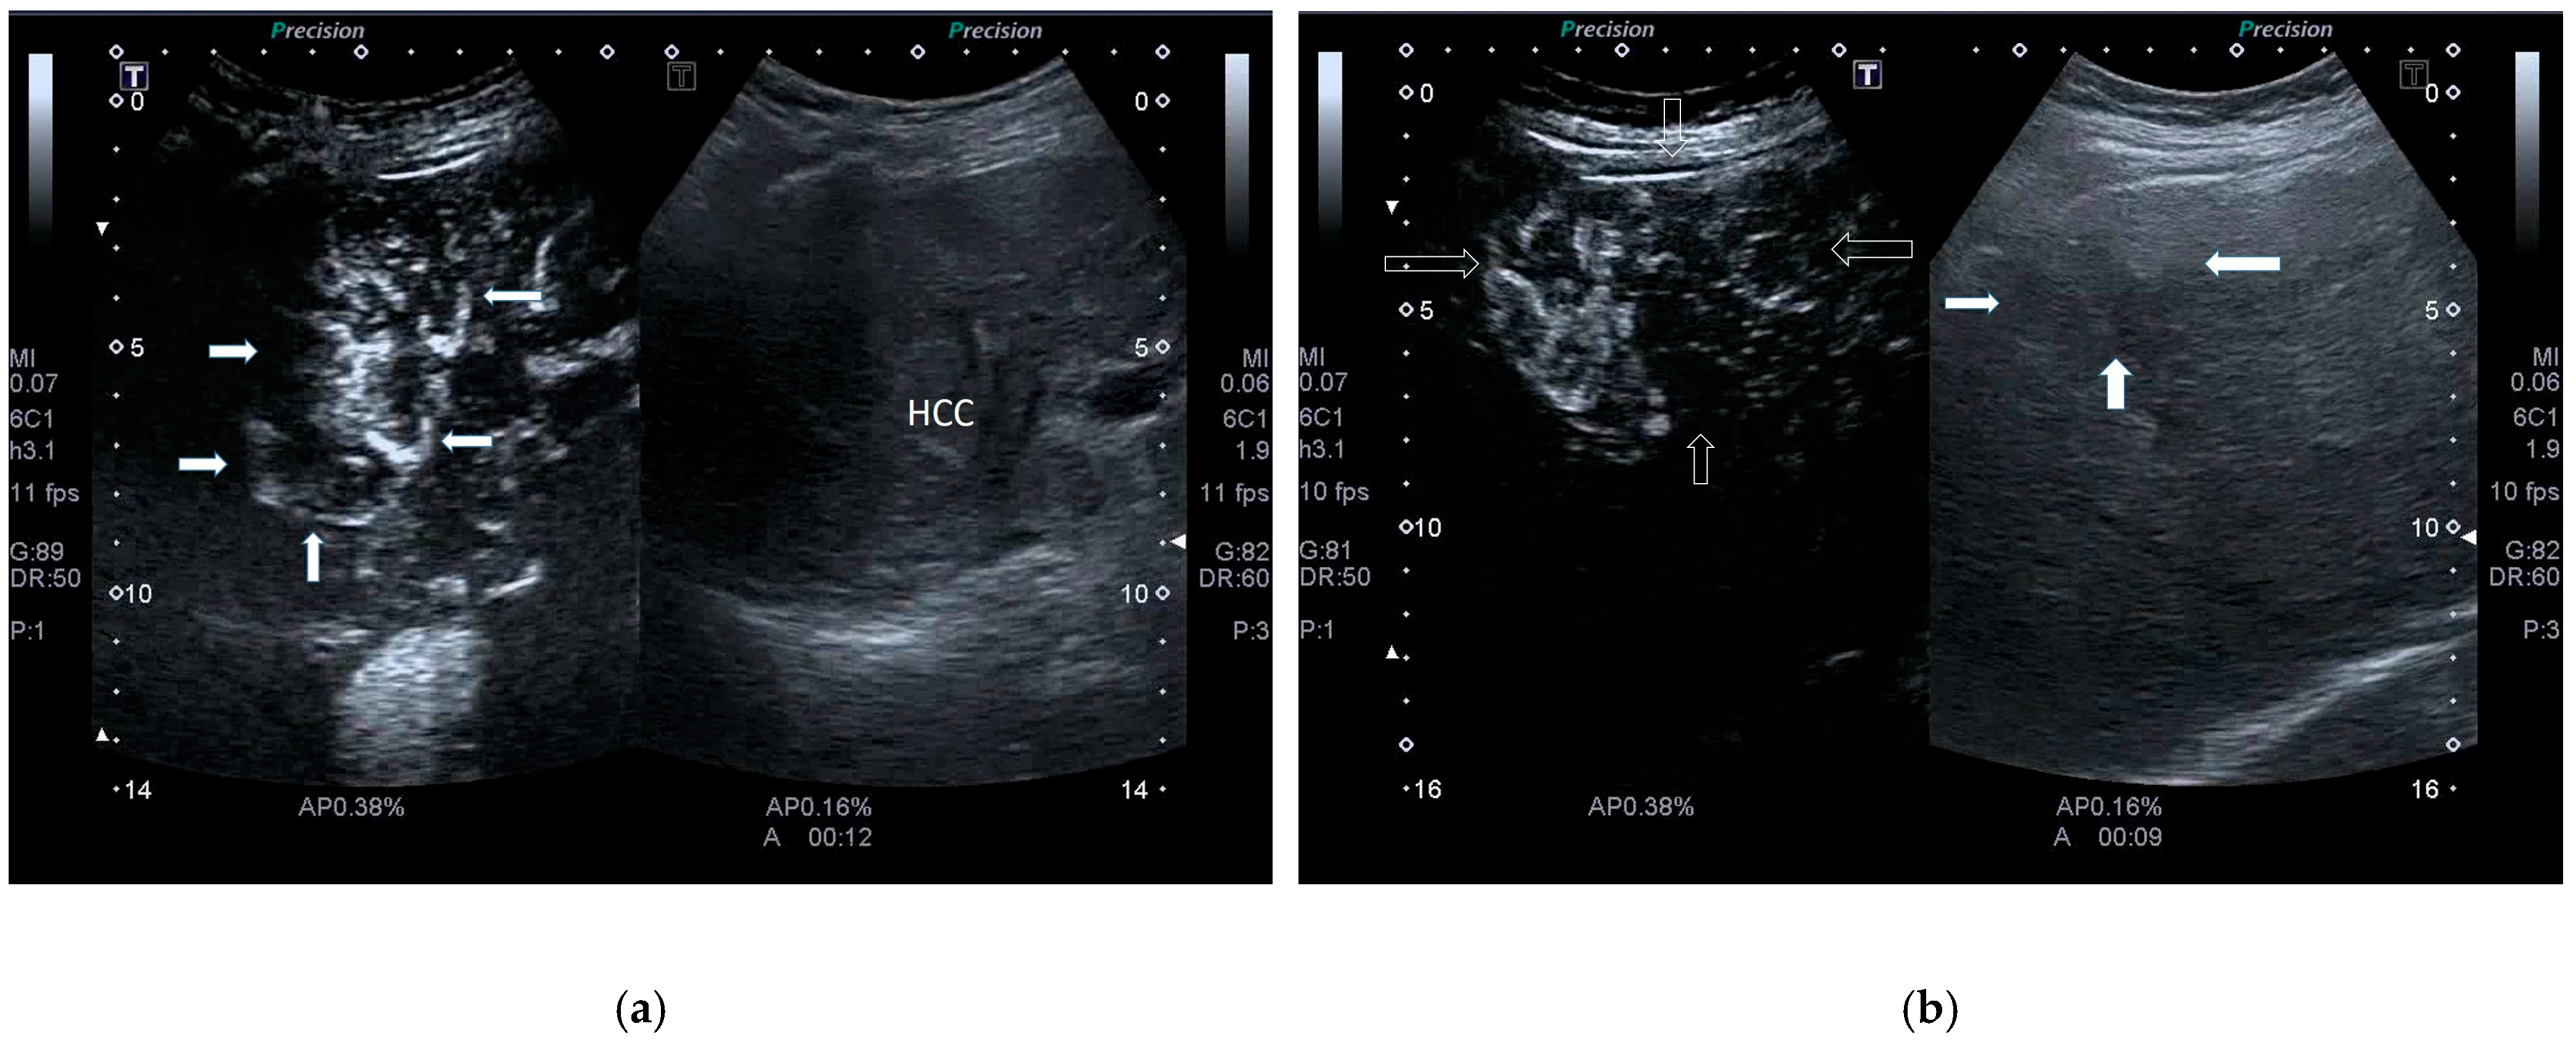

| POST-VIRAL HCC | MASLD HCC |

|---|---|

|

| |

| These characteristics would be focused more on the lack of malignancy rather than HCC. | |

| Need for liver biopsy to make the diagnosis. |